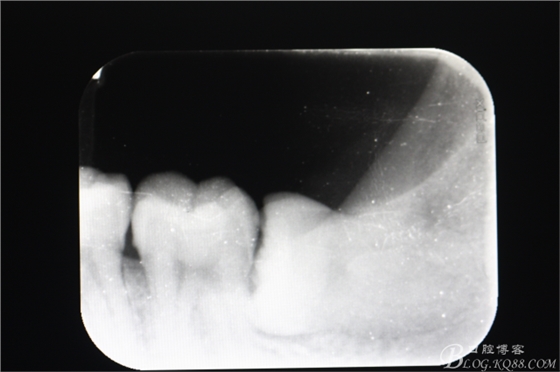

患者、黃x、男、32歲。主訴:左側(cè)下后牙牙齦腫痛不適一周。??茩z查:38水平位、牙冠萌出約1/3,頰側(cè)牙齦輕度紅腫,開(kāi)口度正常,x光:38水平位,牙冠最高點(diǎn)低于37合面,融合根、牙根較長(zhǎng)。診斷:中位水平阻生、治療計(jì)劃:建議拔除38.患者同意手術(shù)方案、簽知情同意書。

圖2.術(shù)前的根尖片:38水平位、牙根較長(zhǎng)、融合根,牙冠最高點(diǎn)低于37合面。